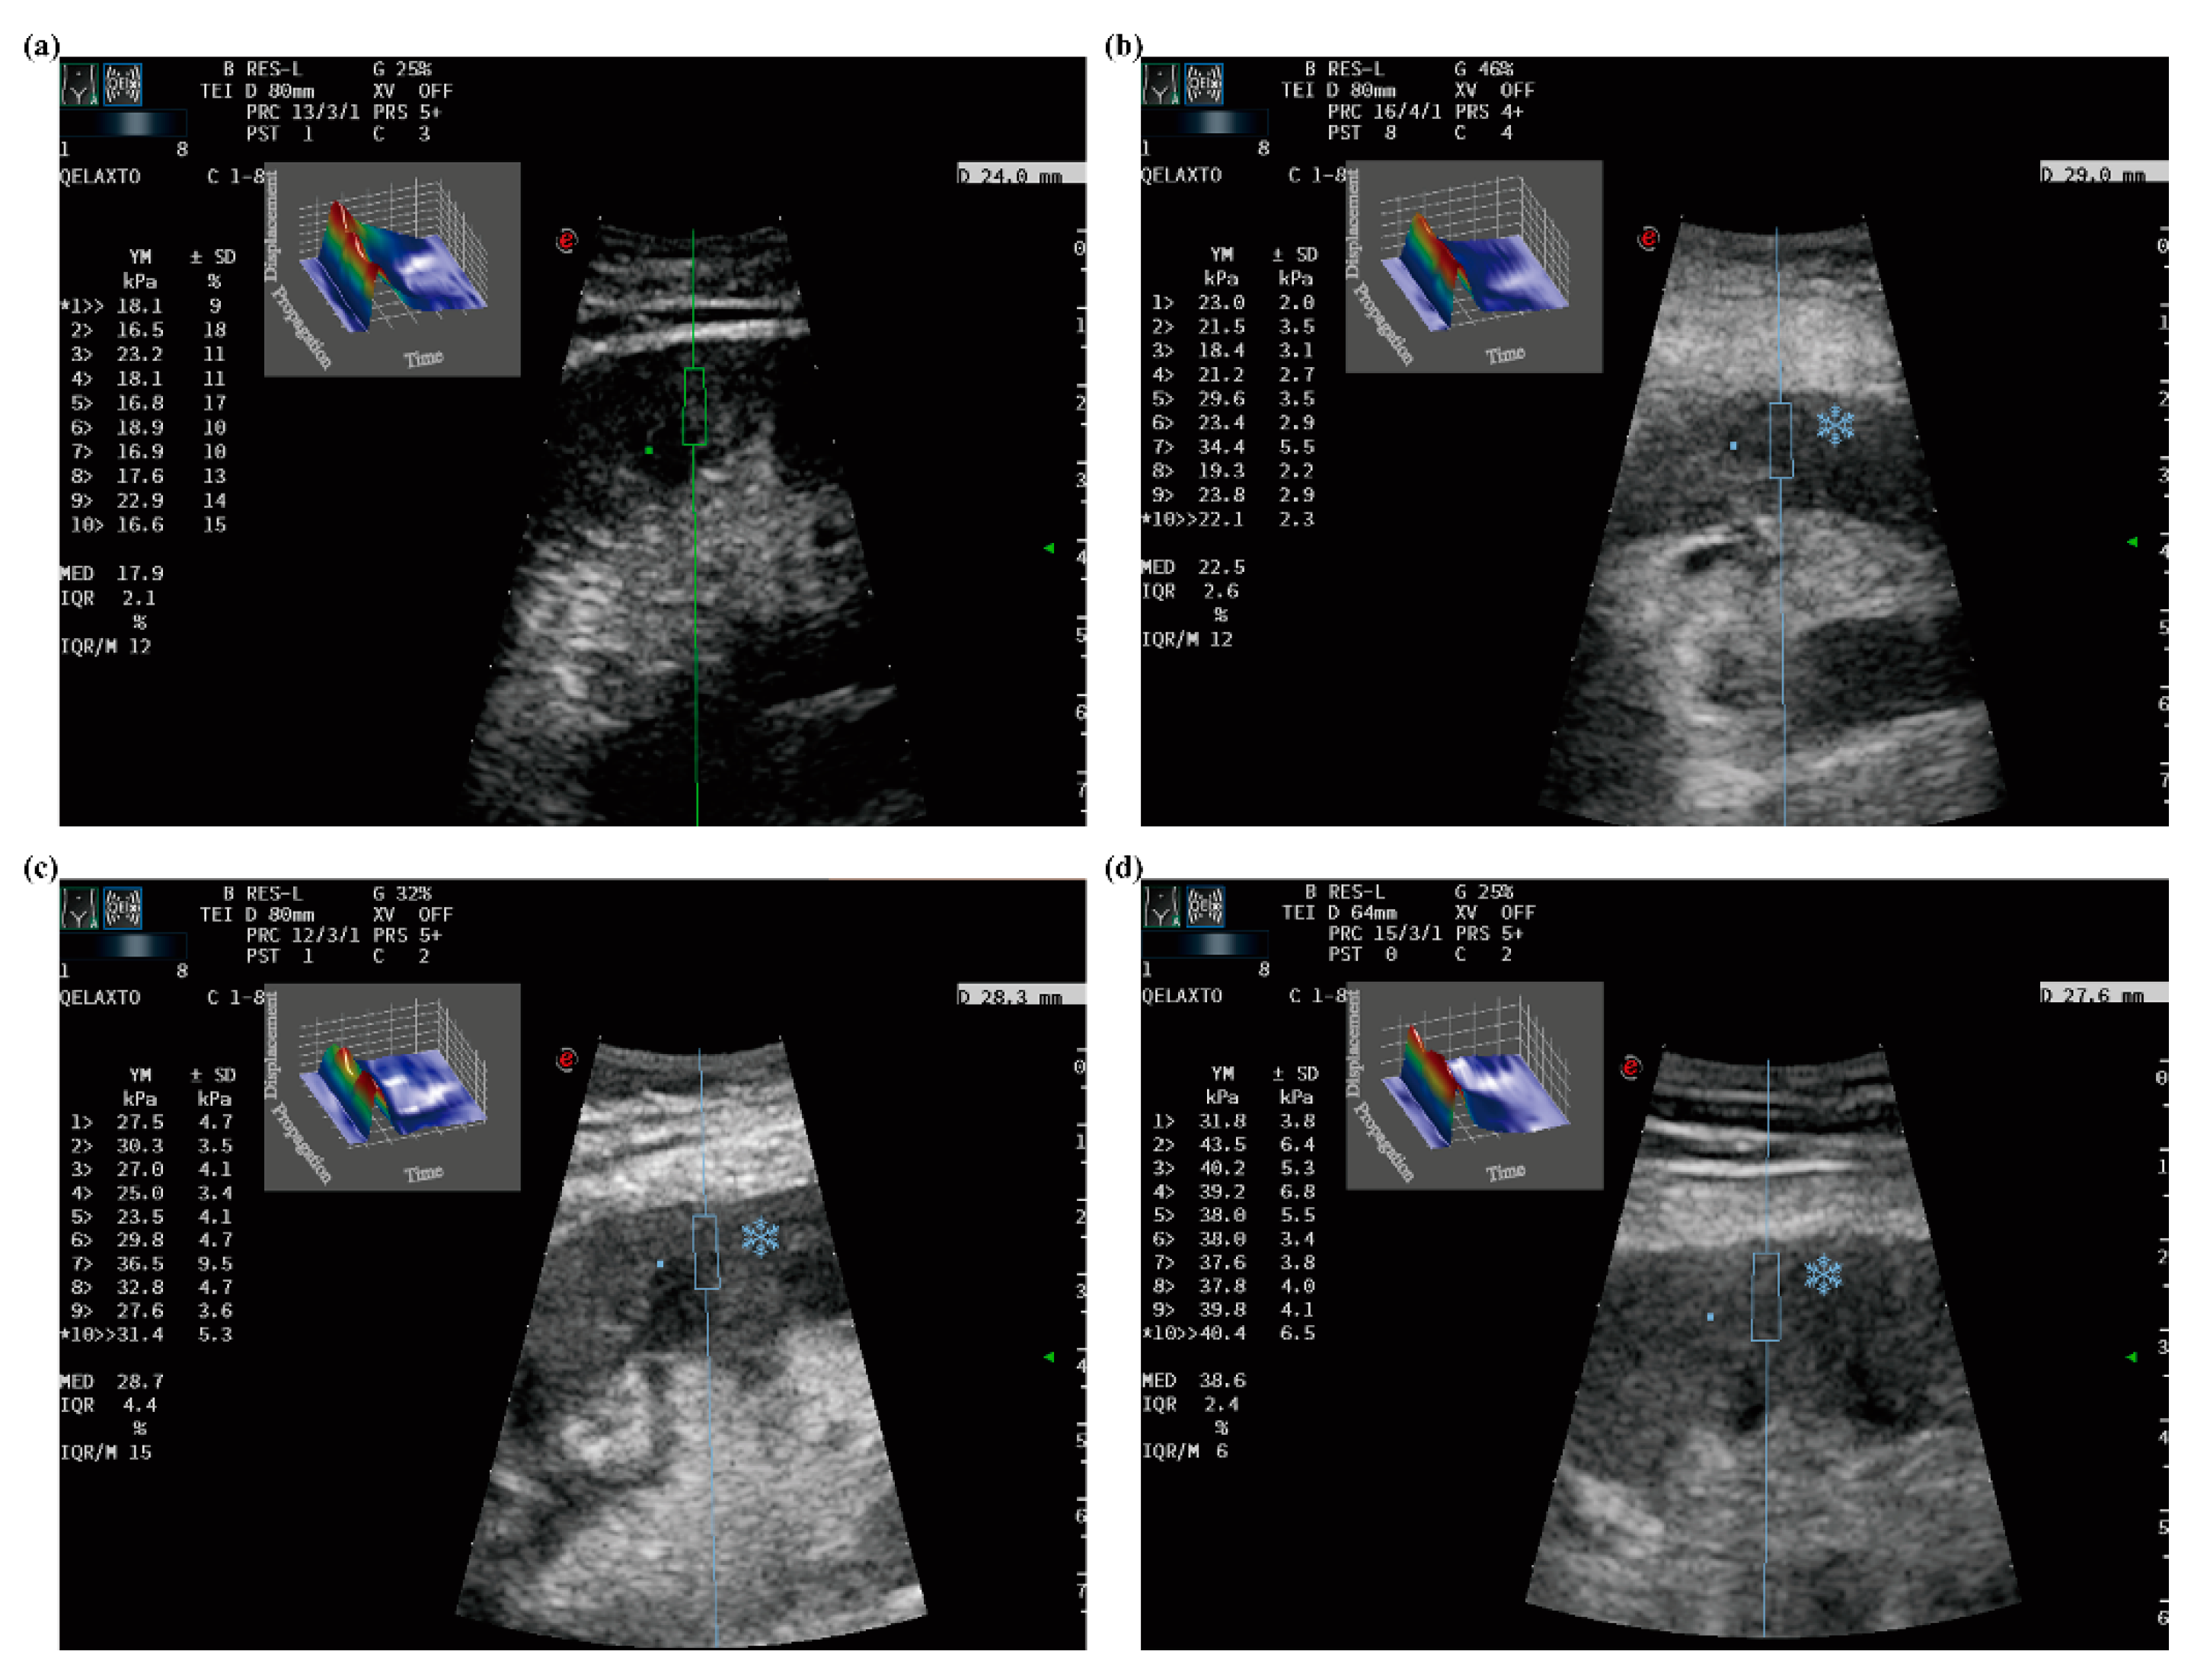

:1. Introduction

2.3. Ultrasound and p-SWE Examinations